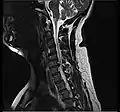

- Magnetic resonance imaging is the gold standard study for confirming a suspected LDH. With a diagnostic accuracy of 97%, it is the most sensitive study to visualize a herniated disc due to its significant ability in soft tissue visualization. MRI also has higher inter-observer reliability than other imaging modalities. It suggests disc herniation when it shows an increased T2-weighted signal at the posterior 10% of the disc. Degenerative disc diseases have shown a correlation with Modic type 1 changes. When evaluating for postoperative lumbar radiculopathies, the recommendation is that the MRI is performed with contrast unless otherwise contraindicated. MRI is more effective than CT in distinguishing inflammatory, malignant, or inflammatory etiologies of LDH. It is indicated relatively early in the course of evaluation (<8 weeks) when the patient presents with relative indications like significant pain, neurological motor deficits, and cauda equina syndrome. Diffusion tensor imaging is a type of MRI sequence used for detecting microstructural changes in the nerve root. It may be beneficial in understanding the changes that occur after herniated lumbar disc compresses a nerve root, and might help in differentiating the patients that need surgical intervention. In patients with a high suspicion of radiculopathy due to lumbar disc herniation, yet the MRI is equivocal or negative, nerve conduction studies are indicated.[44] T2-weighted images allow for clear visualization of protruded disc material in the spinal canal.

MRI scan of cervical disc herniation between C5 and C6 vertebrae